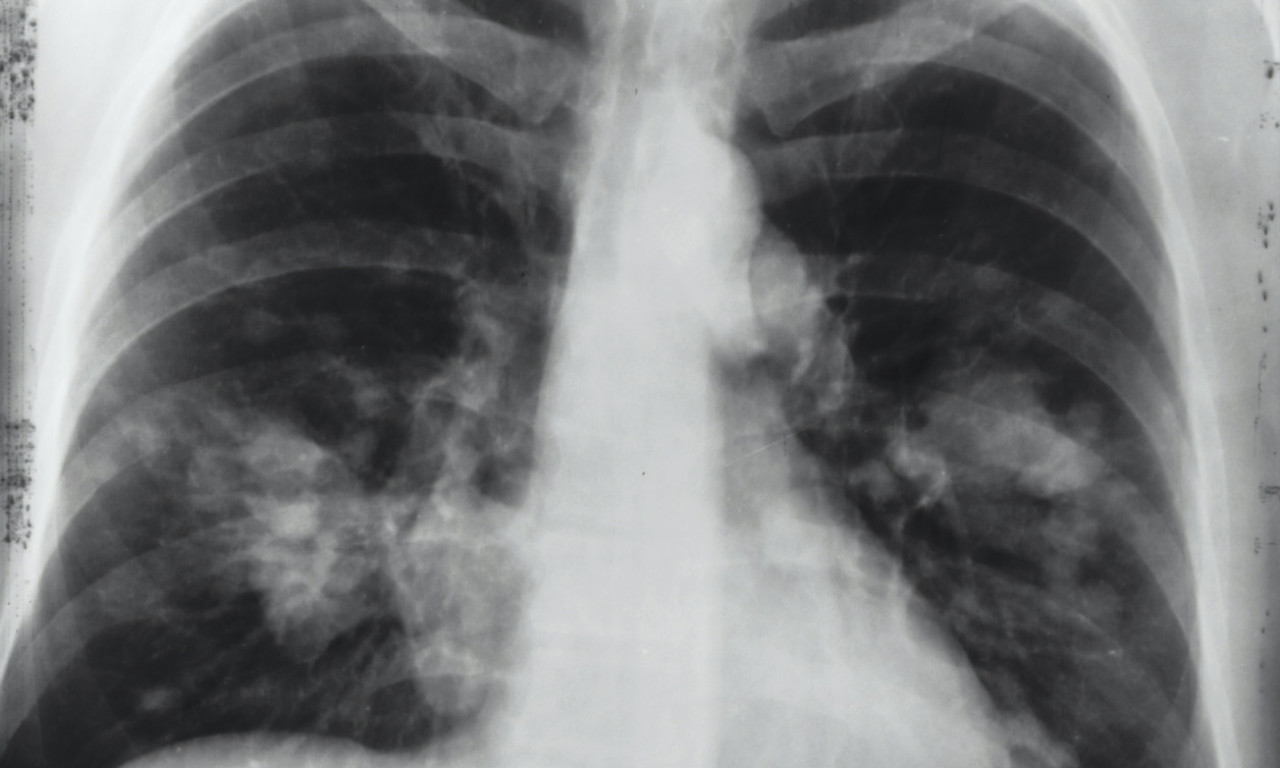

Sa dolaskom jeseni, zdravstveni stručnjaci upozoravaju na pojavu respiratornih virusa, koji uključuju ne samo rino viruse odgovorne za prehlade, već i korona viruse.

- Na jesen dolaze respiratorni virusi, ne samo rino virusi koji uzrokuju prehlade, već i korona virusi. Grip još uvek nije prisutan, ali će doći. Dobra vest je da je trenutna korona varijanta omikronska, koja je vrlo zarazna, ali uzrokuje blage simptome. Zato ne treba da se brinemo - rekao je dr. Andrej Trampuž, dodajući da ova izjava važi i za starije pacijente.

- Korona je malo teža od rino virusa, ali grip je još ozbiljniji. Imamo odlične vakcine i za koronu i za grip, a odgovor na pitanje da li treba da se vakcinišu ljudi je svakako 'da', posebno stariji ili oni sa slabijim imunitetom - dodao je i objasnio o posledicama vakcinacije: